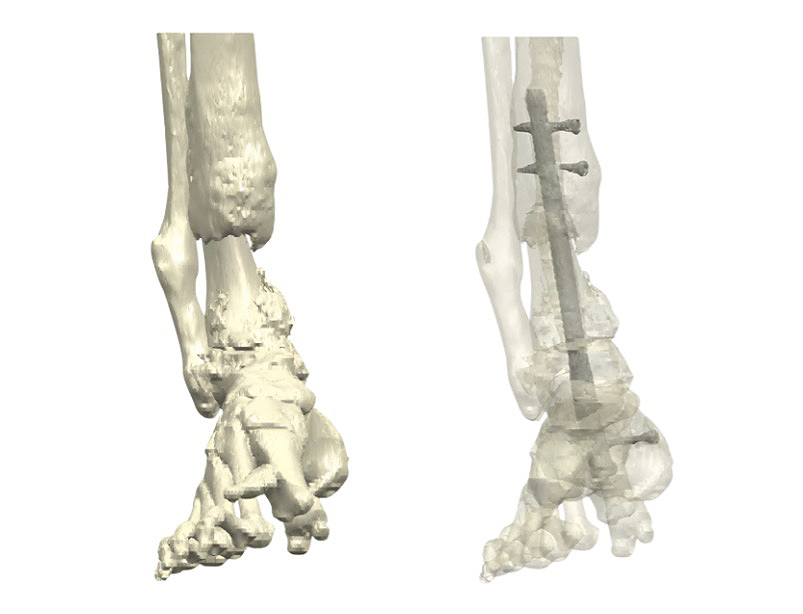

Figure 1: (Left) Preoperative 3D reconstruction of the distal tibia, demonstrating the extensive bone loss that occurred following allograft failure. (Right) Preoperative imaging shows failed fixation, a broken nail, and non-union of the distal tibia.

Massive bone defects of the distal tibia are rare, yet they represent some of the most challenging reconstructive scenarios in

orthopedic surgery. They typically occur after trauma, infection, tumor resection, or—as in this case—after the failure of an allograft.

A 75-year-old male patient weighing 100 kg presented with a history of a distal tibial fracture, which had initially been treated with allograft reconstruction.

Over time, however, the graft failed, resulting in loss of fixation, instability, and non-union. This resulted in mechanical insufficiency and functional impairment,

causing significant pain and limiting weight-bearing capacity.